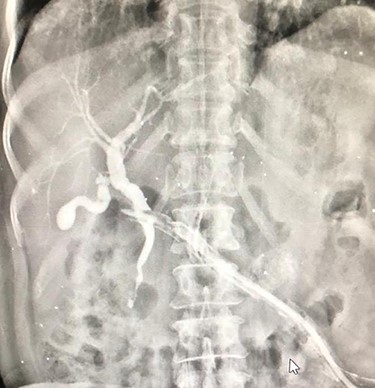

An 81-year-old female, a known case of idiopathic acute necrotizing pancreatitis, had been on percutaneous catheter drainage (PCD) for infected pancreatic necrosis at 6 weeks of onset (Fig. 1). On the eight day, she required a second PCD insertion for persistent lesser sac collection and sepsis. During PCD intervention, there was active bleeding from the catheter site which led to emergency pancreatic necrosectomy, hemostasis from the bleeding gastrocolic ligament vessel, closed lesser sac drainage and feeding jejunostomy. After surgery, she did well and was discharged on Day 15. The lesser sac drain output was clear with a raised amylase level. On the 24th day after surgery, she was readmitted for the high (300 ml/day) bilious drain output (Fig. 2). She denied any fever, vomiting or abdominal pain. She was hemodynamically stable without abdominal distention or tenderness. Her blood investigations revealed leukocytosis (13 600 cells per cubic milliliter), but normal renal function tests and serum chemistry. A diagnosis of the duodenal fistula was presumed and was kept nil per oral, intravenous fluids, antibiotics and initiation of feeding jejunostomy. She was doing well for the next 1 week with a good appetite. Contrast computed tomography (CT) excluded any peripancreatic collections, and importantly there was no oral contrast extravasation in the para-duodenal region. The drain output was persistently high (300–350 ml/day) and bilious with normal fluid amylase activity. We requested for fistulogram, which surprisingly revealed an external biliary fistula from the distal common bile duct (Fig. 3). Endoscopic retrograde cholangiopancreatography (ERCP) and bile duct stenting (7Fr × 10 cm double pigtail plastic stent) was performed, which led to the closure of the fistula over the next 7 days. At a 6-month follow-up, the patient is doing well.

Fistulogram from the lesser sac drain showing biliary tree opacification.